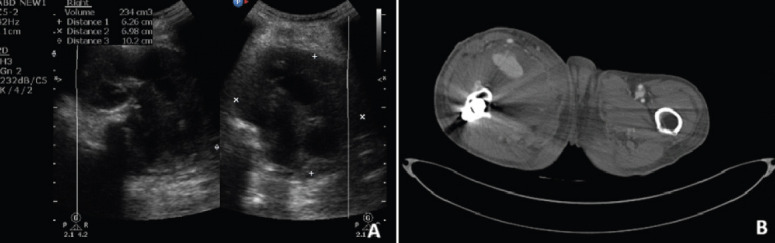

Case report: An 80-year-old male patient presented 3 weeks post-surgical fixation for an intertrochanteric fracture with pain and swelling of the thigh. Radiological evaluation revealed a pseudoaneurysm of the profunda femoris artery, which was managed by the cardiothoracic and vascular surgery team.